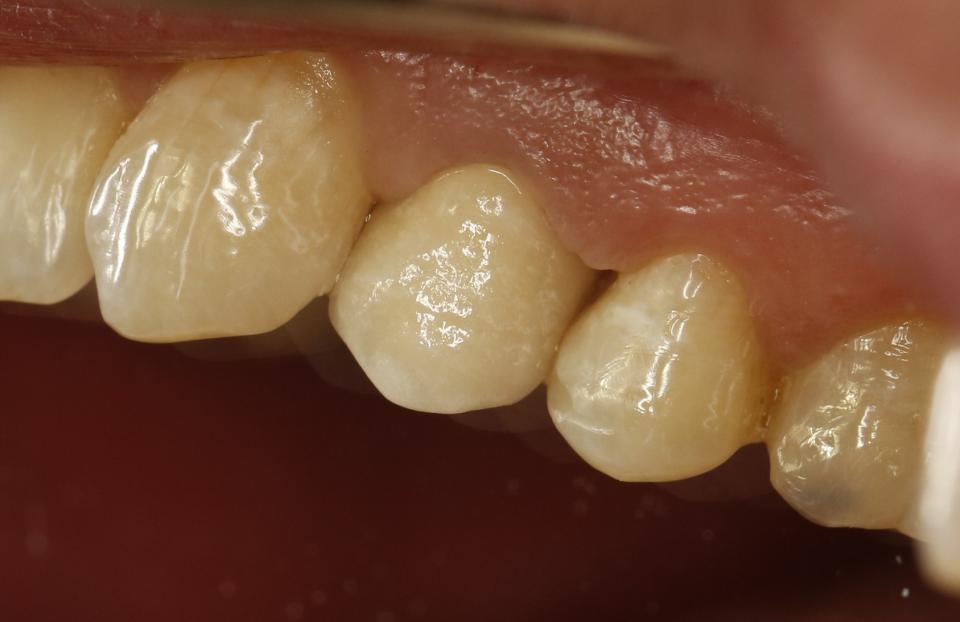

paraschyk1 Опубликовано 16 октября, 2015 Автор Опубликовано 16 октября, 2015 Выпал недавно реставрированный жевательный семерка вместе со штифтами. Т.е. там остались одни корни, над десной ничего от зуба нет. Было 2 штифта, реставрация + обычная простая коронка сверху. Все это аккуратно выпало. Один стоматолог говорит, что даже браться не будет, мол через годик снова отвалится, только вырывать. Другой говорит, что здоровый корень, какой нафиг рвать, только делать. Ниже вариант спасения зуба,когда полная жопа. Такой зуб может бегать пять лет и более.

paraschyk1 Опубликовано 13 декабря, 2015 Автор Опубликовано 13 декабря, 2015 Починил форумчанена после неудачного лечения.